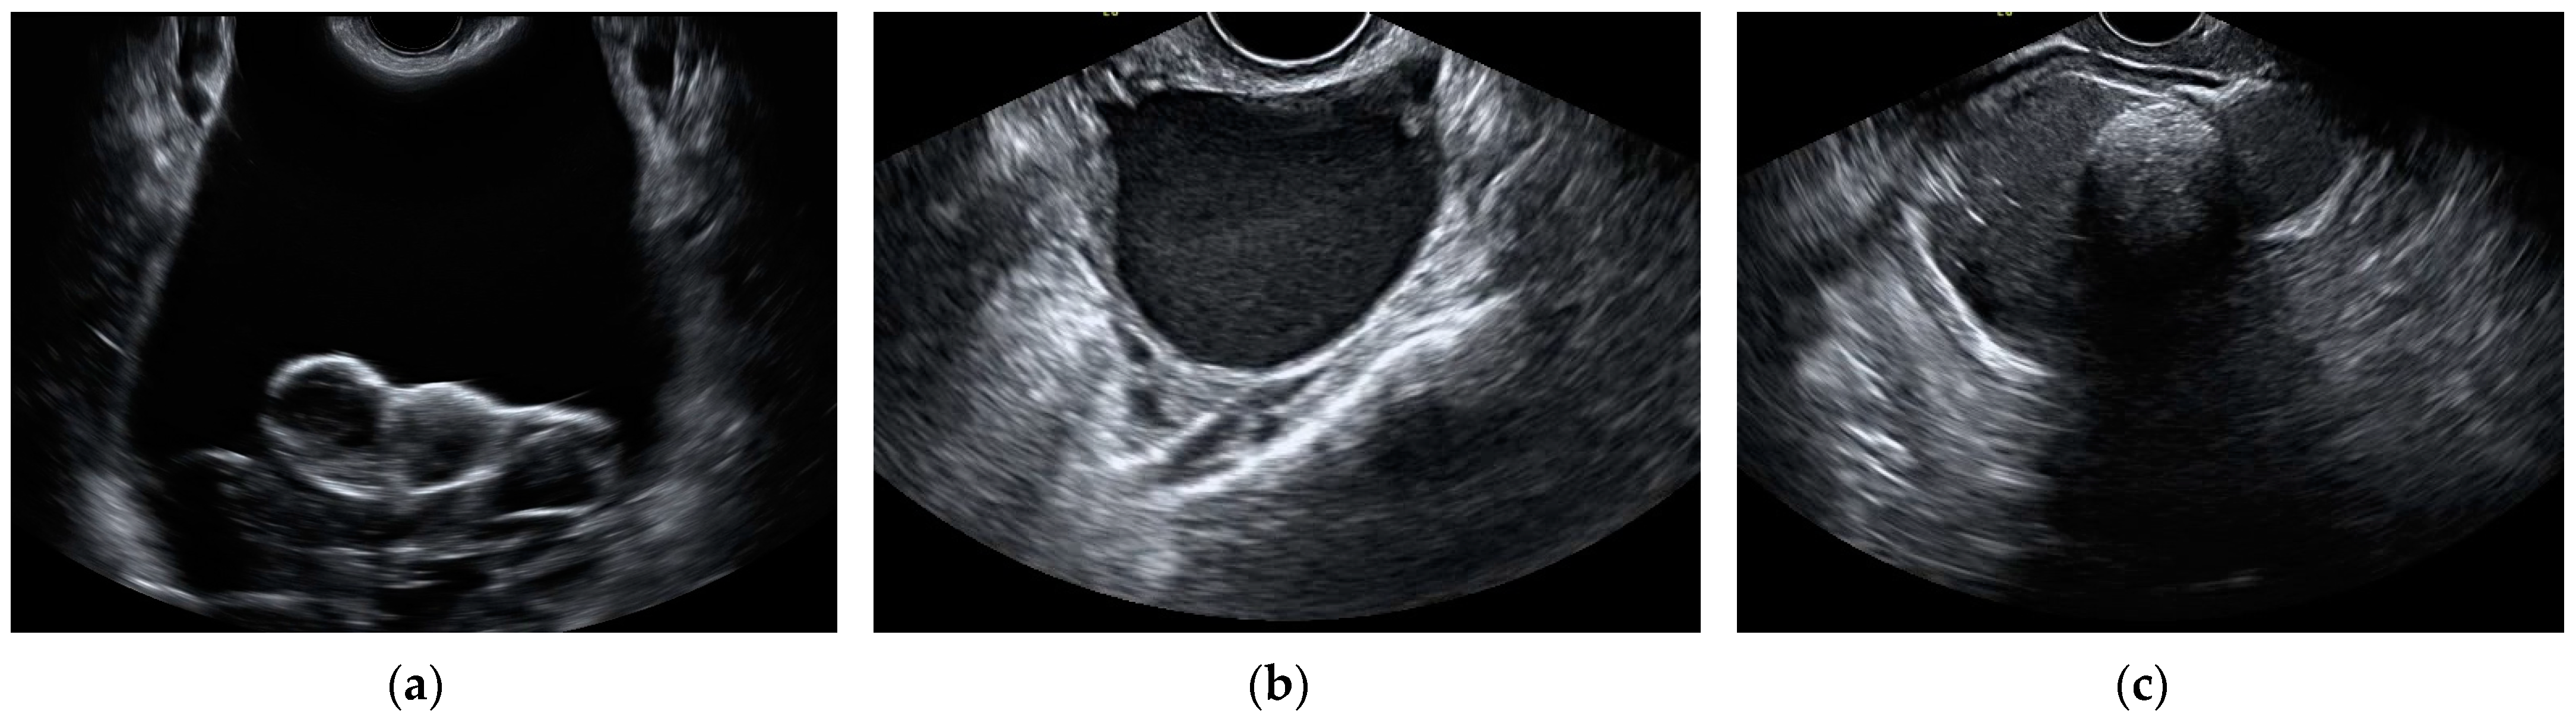

2.2. Ultrasound Assessment